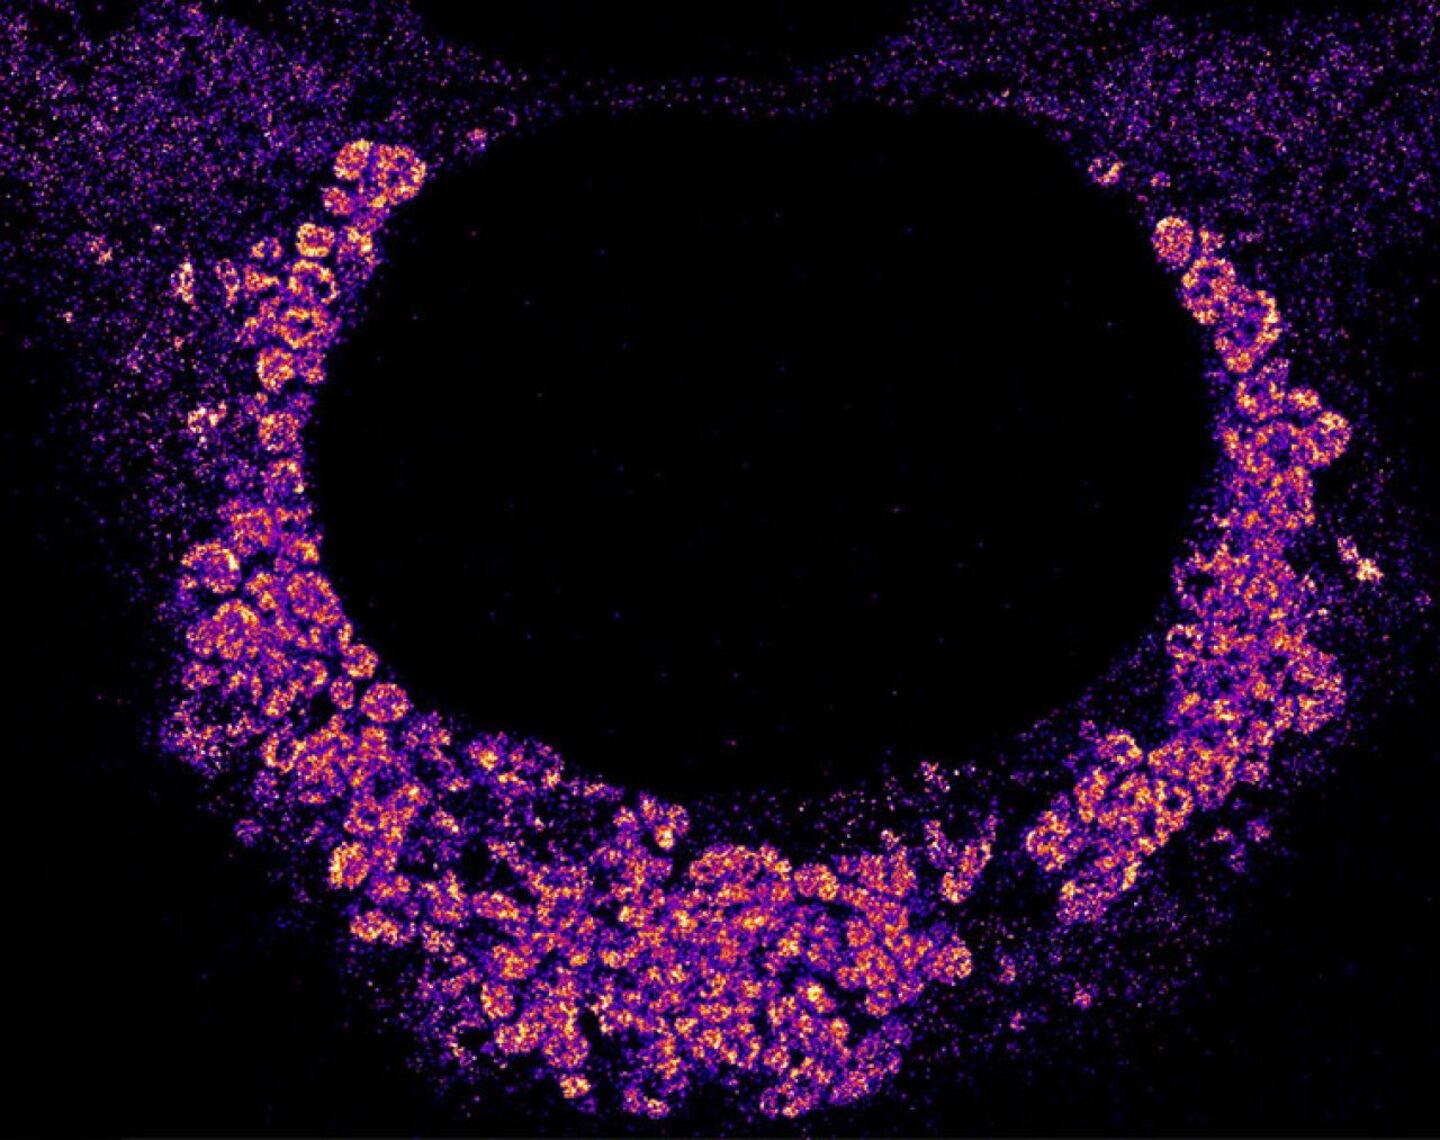

And in 2024, a team of scientists at Stanford University examined how the COVID-19 virus replicates inside human cells. Using fluorescent tags to label the virus's genetic material, biophysicist Leonid Andronov and colleagues found that SARS-CoV-2 makes a bubble with a double membrane in which it copies its genetic material. This probably prevents destruction by the cell, Andronov says.

L. Andronov et al // Nature Communications 2024